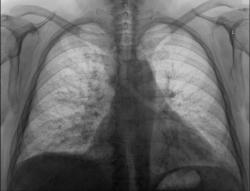

Добрый день коллеги! Сегодня проглядывал снимочки легких, по просьбе своей коллеги, с целью исключения метастазов и увидел  представленную картину. Пациентка 50 лет, лежит  в стационаре с диагнозом: Злокачественное новообразование яичника? Мts в надключичные лимфатические узлы. Мысли сразу про лимфогенные метастазы,  поглядел сразу в архиве ФЛГ от 11.08.09г. два первых снимка, два последних сегоднишним днем. Ваше мнение?

Два последних снимочка это сегоднишние цыфровые рентгенограммы, КТ-у нас пока вышло из строя. По УЗИ находят образование в почке и яичнике.

Я бы не рискнул "увидеть" на представленных Вами снимках лимфогенные метастазы (не смотря на анамнез). На мой взгляд, динамика по снимкам несущественна, да и та связана с застойными изменениями в легких. А на фоне застоя лимфогенные метастазы по рентгенограмме отдифференцировать очень трудно.

В том то и дело уважаемый Alex застойные изменения в МКК, минимальные, а картина похожа на лимфастаз.

Другое дело, что если бы я нашел ФЛГ прошлого года, и исключил выраженный пневмосклероз, попробую завтра ещё полазить, может найду.

Ну что-же, Вам на месте виднее. Тогда хотя бы срединную томограмму попробуйте сделать, лучше корни рассмотрите, да и лимфоузлы средостения при лимфогенном метастазировании поражаются чаще, чем не поражаются.

Поддерживаю пост Alex, в той части, что симптоматика по флюорограмме за лимфогенные  метастазы неубедительная(возможно на КТ их будет видно). Усиление лёгочного рисунка, вероятно не связано с застойными изменениями( нет признаков гипертензии вен верних долей( симптома "оленьих рогов"), который рассматриваеться, как I стадия левожелудочковой недостаточности).